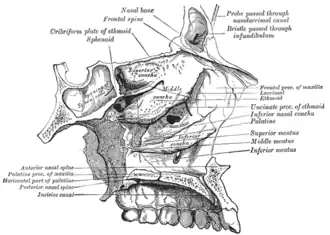

Roof, floor, and lateral wall of left nasal cavity.

Roof, floor, and lateral wall of left nasal cavity. -

- Atlas image: rsa1p7 at the University of Michigan Health System – "Nasal septum, lateral view"